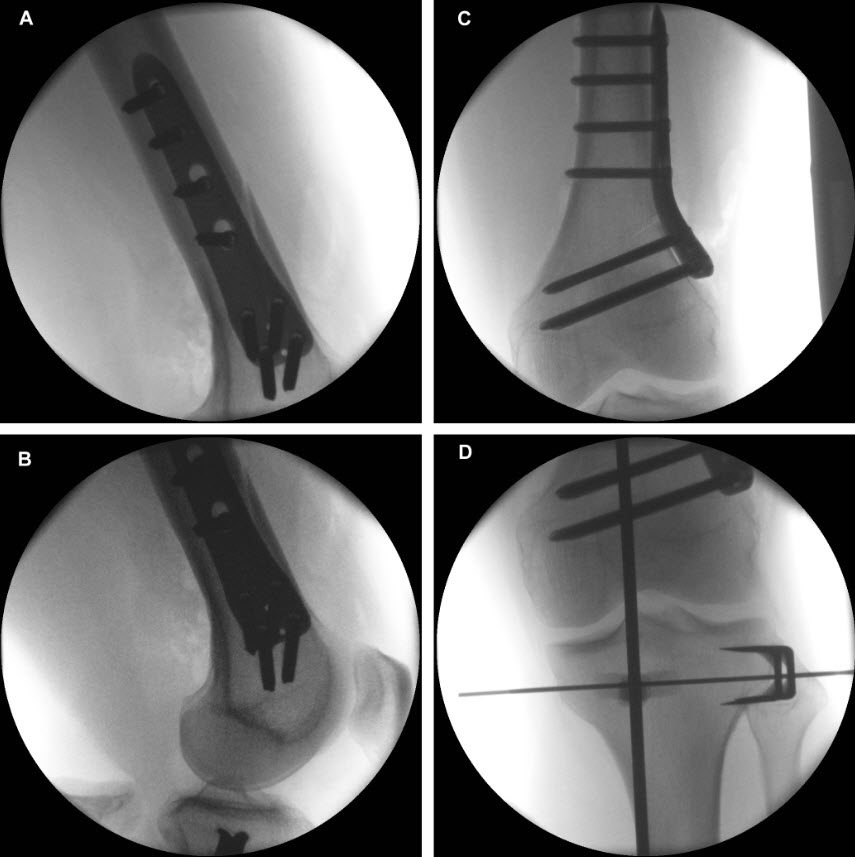

The TomoFix Anatomical Medial High Tibial Plate is contoured to provide an anatomical fit. When compared with the TomoFix Standard and small plates, the new design is intended to reduce both implant prominence

and postoperative implant irritation. Fig 1 shows x-rays from one patient.

Not only does the new TomoFix Knee Osteotomy System contain a new MHT plate with more anatomical features, it also includes new osteotomy instrumentation intended to improve both surgical accuracy and procedural efficiency. The new instrumentation is compatible with the existing Standard and small TomoFix Medial High Tibia plates. Fig 4 shows a patient with post-traumatic deformity after a proximal tibial fracture (at the 6-week follow-up after open wedge HTO in descending technique and fixation with the TomoFix MHT anatomical plate).